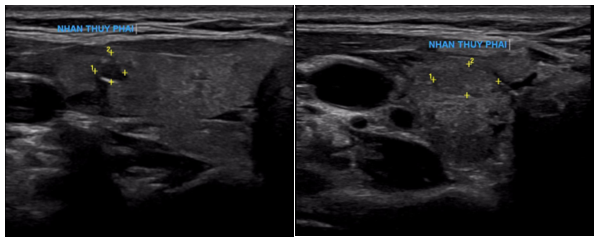

Siêu âm:

Thùy phải: kích thước bình thường, nhu mô có vài nhân hỗn hợp âm, lớn nhất kích thước 3x3mm và có nhân giảm âm, vôi hóa ngoại vi kích thước 3x4mm (TIRADS 4), nhân đồng âm bờ đều, kích thước 4x6mm.

Hình 1: Hình ảnh nhân giảm âm thùy phải tuyến giáp (TIRADS 4)